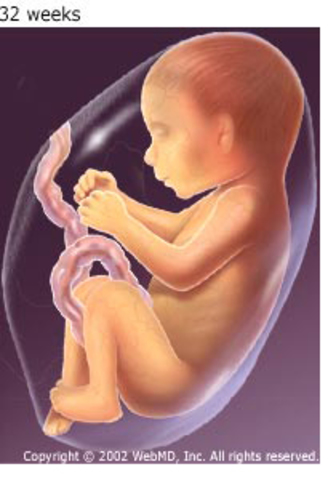

• Eighth month

Eighth month

With its major development finished, the fetus gains weight very quickly.

Bones harden, but the skull remains soft and flexible for delivery.

The different regions of the brain are forming.

Taste buds develop, and the fetus can taste sweet and sour.

The fetus may now hiccup.